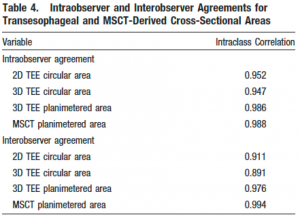

一方で心エコーの弱点としては、再現性の低さや検者間誤差、石灰化/人工物などに伴うアーチファクト、被検査者側要素(体位、体型、エコーウインドウの差異など)による描出困難例の存在などが挙げられる。下表は大動脈狭窄患者における大動脈基部のTEEとCTにおける評価の比較である。3D TEEではかなり改善されているとはいえ、誤差の面では他のModalityに劣ると言わざるを得ない。

(文献4より引用)

(文献4より引用)